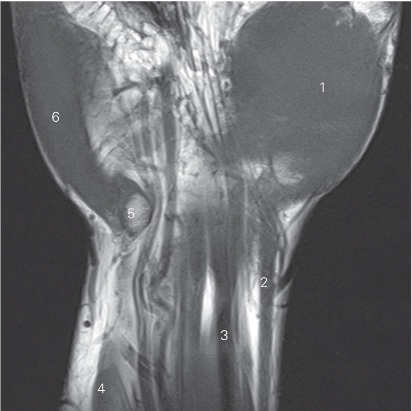

图4-52 经豌豆骨的冠状断层MR T1加权图像

1 大鱼际 thenar

2 桡侧腕屈肌腱 tendon of flexor carpi radialis

3 指浅屈肌腱 tendon of flexor digitorum superficialis

4 尺侧腕屈肌 flexor carpi ulnaris

5 豌豆骨 pisiform bone

6 小鱼际 hypothenar